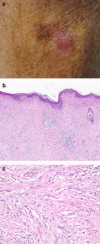

In the initial period after melanoma was recognised as a disease entity in the early 1800's, it was subclassified on the basis of its presumed origin (from a precursor naevus, from a melanocytic precursor lesion acquired during adult life or in previously blemish-fee skin). In 1967 the eminent American pathologist, Dr Wallace Clark, proposed a histogenetic classification for melanoma in which the disease was subdivided predominantly on the basis of histopathological features of the intra-epidermal component of the tumour adjacent to any dermal invasive component. The subtypes were superficial spreading melanoma (SSM), lentigo maligna melanoma (LMM) and nodular melanoma (NM). Whilst additional entities, including acral lentiginous melanoma, mucosal melanoma, desmoplastic melanoma and naevoid melanoma have since been recognised, SSM, LMM and NM remain in the latest (2006) version of the WHO melanoma classification. Clark's histogenetic classification has been criticised because the criteria upon which it is based include clinical features (such as the site of the melanoma) and non-tumourous histopathological features (such as the character of the associated epidermis and the degree of solar elastosis) and also because of overlap in defining features, lack of an independent association with patient outcome and minimal relevance as a determinant of clinical management. However, such criticisms fail to acknowledge its importance in highlighting the myriad of clinical and histological guises of melanoma, which if not recognized by clinicians and pathologists will inevitably lead to a delay in diagnosis and a concomitant adverse clinical outcome. Recently, mutually exclusive oncogenic mutations in melanomas involving NRAS (15-20%), BRAF (50%), CKIT (2%), and GNAQ/GNA11 (50% of uveal melanomas) have been identified. This might herald the beginning of a new molecular classification of melanoma in which the biologically distinct subsets share a common oncogenic mechanism, behave clinically in a similar fashion and require similar clinical management. These discoveries are already being successfully exploited as therapeutic targets in clinical trials of metastatic melanoma patients with promising activity. Whilst there remains much to be discovered in this rapidly evolving field, there is already great optimism that more rational and effective therapies for melanoma patients will soon be widely available.